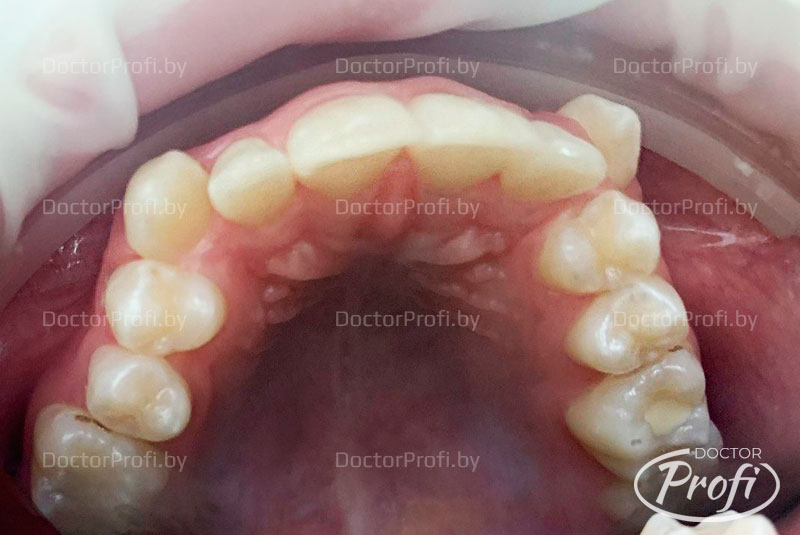

Родители пациентки обратились в клинику с жалобами на неэстетичный зубной ряд. На консультации у ортодонта были выявлены следующие проблемы с прикусом: дистальный глубокий прикус, буккально-перекрестный справа, сужение и укорочение верхнего зубного ряда, вестибулярное положение клыков верхней челюсти с дефицитом места в зубном ряду.

- Проведена коррекция прикуса. Улучшена форма зубных рядов и положение зубов.

- Исправлено вестибуляное положение клыков.

В результате ортодонтического лечения пациент обрел красивую улыбку, правильный прикус, ровные и здоровые зубы.